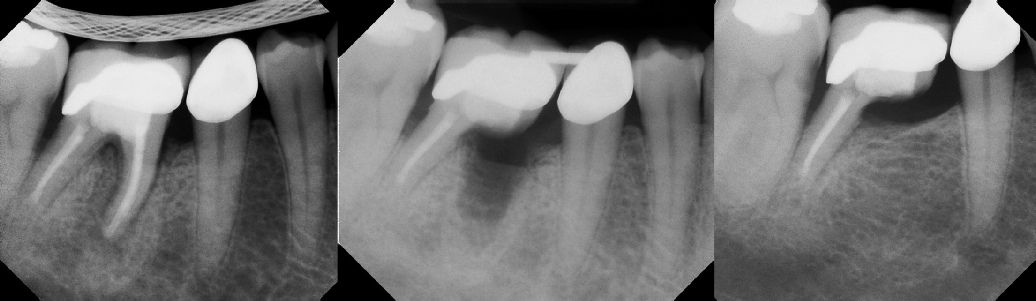

COMPLICATED ANATOMY LARGE LESIONS CALCIFIED CANALS PERFORATION / RESORPTION SEPARATED INSTRUMENTS SURGICAL CASES RETREATMENT / pOST REMOVAL OPEN APICES ACCESS THRU CROWNS Root Canal Case Portfolio

Apicoectomy - Surgical Root Canal Pre-op (post trauma) Coronal segments obturated Apical segments surgically removed 3 years